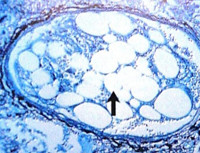

Синдром жировой эмболии — одно из наиболее грозных ранних осложнений тяжелой политравмы. По данным литературы, гистологически определяемые жировые капли выявляются в 80-90 % случаев у пациентов с переломами костей конечностей, однако, при благоприятном течении посттравматического периода у подавляющего большинства пострадавших жировые капли самостоятельно утилизуются. Лишь у 1-4 % пострадавших, в силу определенных причин, развивается клинический синдром жировой эмболии, нередко (до 10-36 % случаев) приводящий к фатальным последствиям [5, 6, 8]. Вероятность развития синдрома жировой эмболии при травме определяется тяжестью и характером травматических повреждений, адекватностью и сроками оказания специализированной помощи, индивидуальными особенностями реактивности организма пострадавшего.

По определению ряда авторов, синдром жировой эмболии (fat embolism syndrome) — это тяжелое, угрожающее жизни состояние, обусловленное множественной окклюзией кровеносных сосудов каплями жира — жировыми эмболами — недифференцированными липидными массами, жировыми клетками, липидными комплексами, размером более 6-8 мкм. Синдром жировой эмболии (СЖЭ) нередко протекает под маской пневмонии, отека головного мозга, респираторного дистресс-синдрома взрослых, сердечно-сосудистой недостаточности, способствуя значительному увеличению летальности. Вероятность развития СЖЭ при травме определяется тяжестью и характером травматических повреждений, адекватностью и сроками оказания медицинской помощи, индивидуальными особенностями организма пострадавшего [5, 9, 10].

Инструментально-лабораторные критерии диагностики развивающейся и развившейся жировой эмболии в ряде случаев весьма затруднительны и проявляются на поздних стадиях развития осложнения. Среди них необходимо отметить: наличие капель свободного жира в биологических жидкостях (жир в моче). Диффузная инфильтрация легких (симптом «снежной бури») при рентгенологическом исследовании. Стойкая анемия (по причине патологического депонирования крови и токсического распада эритроцитов). Характерные изменения глазного дна (на фоне отечной сетчатки выявляются округлые облаковидные белесоватые пятна). Изменения в моче характерные для гломерулонефрита; азотемия. Повышение процентного содержания жира в альвеолярных макрофагах в первые сутки после травмы.